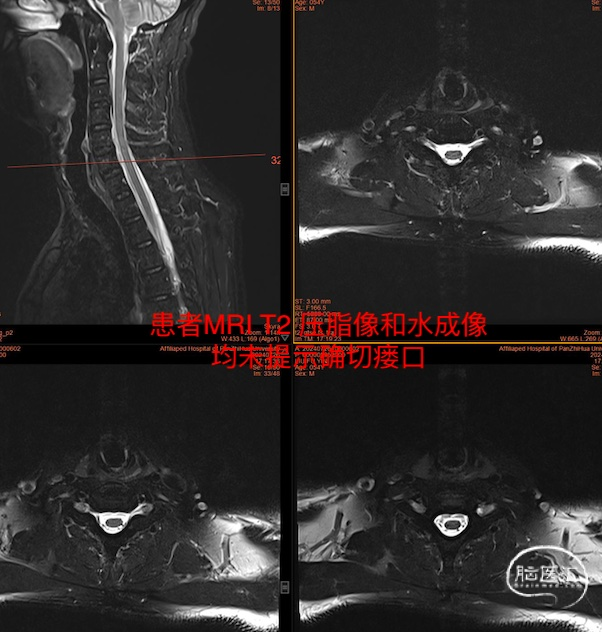

入院后头部MRI平扫及增强均未见异常,脊柱MRIT2压脂扫描如下图:

随后的水成像检查也未见异常。